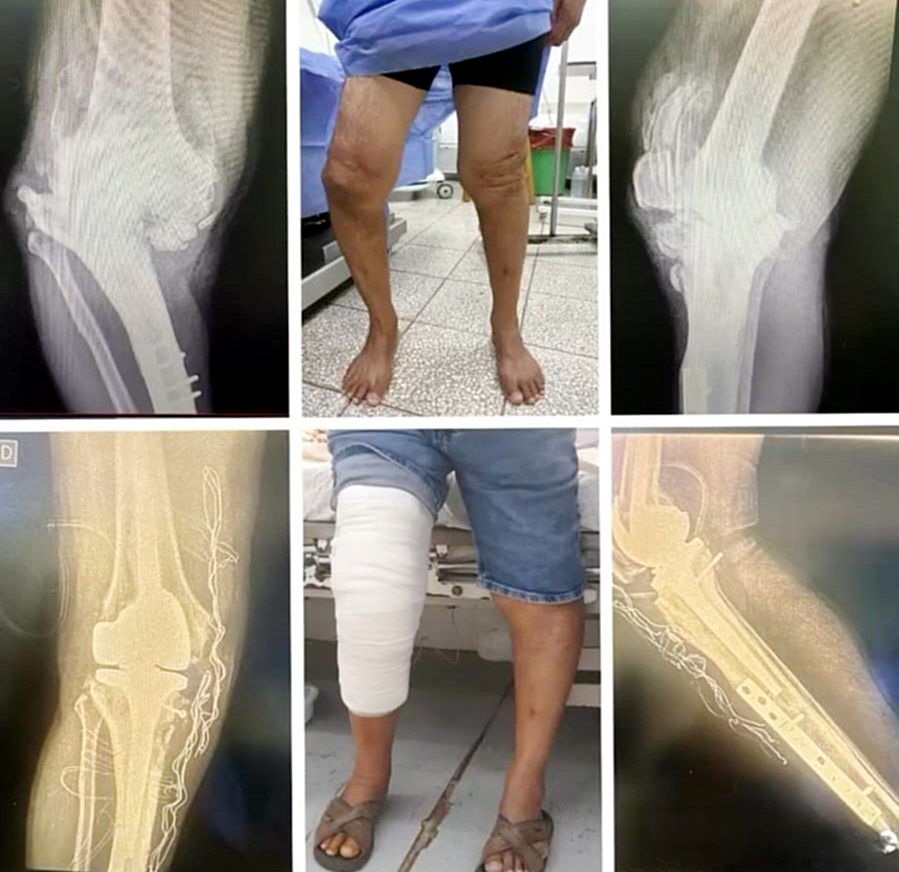

“Entonces vimos la posibilidad de llevar a cabo la cirugía de la rodilla derecha al constatar la gran deformidad y artrosis que presentaba el paciente. El plan consistió en realizar un remplazo articular y corregir la deformidad con una prótesis total de tipo bisagra”.

“Con la colaboración del Departamento de Servicios Quirúrgicos de IPS Central pudimos realizar la cirugía de forma exitosa. El paciente presentaba un un varo y artrosis severa (grado IV) en la rodilla derecha. Una enfermedad degenerativa de la rodilla que con una prótesis primaria no se podría corregir la deformidad. Sin embargo, los especialistas de cirugía de rodilla de IPS ya realizan este tipo de cirugías de prótesis para grandes deformidades” señaló el médico.

“Si bien el señor Jobino tenía una deformidad bien pronunciada. Nuestro objetivo como traumatólogos es buscar que ambas rodillas estén compensadas (restablecer el eje de carga, recuperar la función y calmar el dolor)”.

“Gracias a la innovación y la tecnología que se dispone podemos ofrecer mayor calidad de vida a los pacientes para que puedan recuperar su rutina diaria. Don Jobino es uno de los primeros en realizarse esta cirugía en el Hospital Central. Y así como Él acudió al servicio, otros pacientes también pueden recurrir al Hospital Central, en donde se les puede brindar los cuidados necesarios. Y mejorar su calidad de vida”.